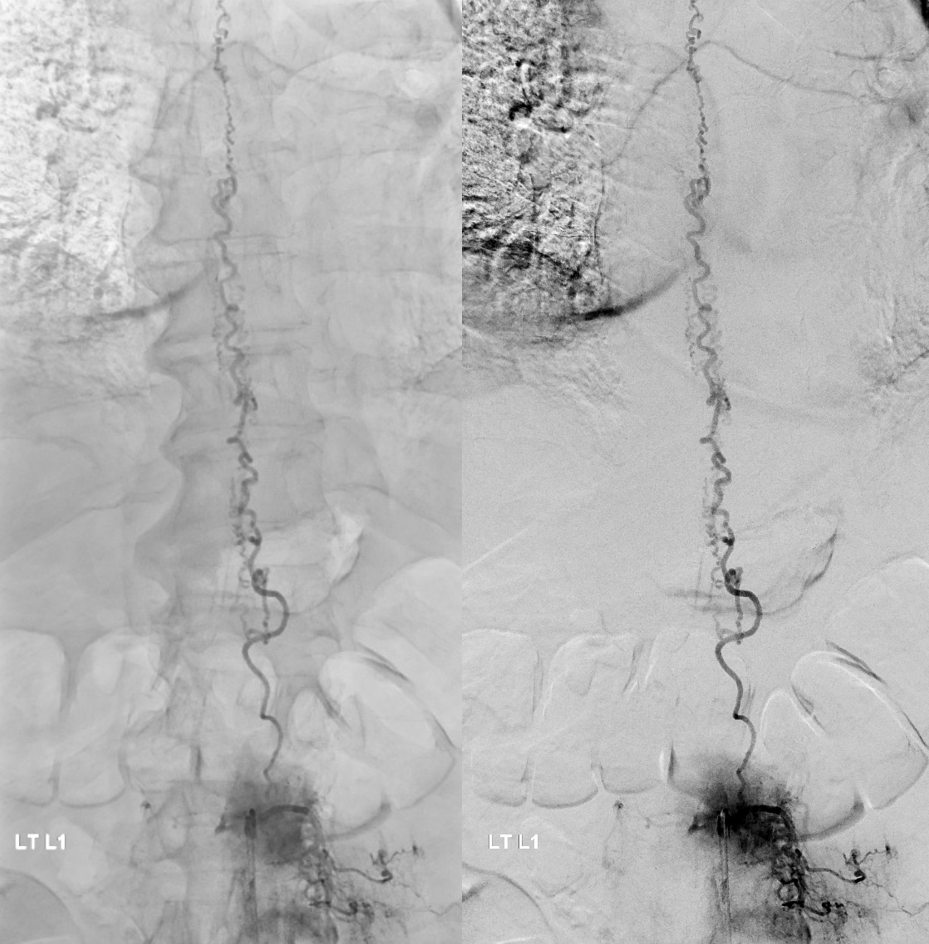

All dural fistula pathophysiology, and spinal too, consists of two key factors. One is fistula. The other is degree of venous congestion. Normal spinal venous anatomy consists of multiple radicular veins which drain the cord via nerve root sleeve / foramen into the epidural venous plexus. These veins are almost always deficient (missing from getgo, thrombosed, both?) in patients with spinal dural fistulas. Could it be that venous deficiency comes first, and fistula emerges later? Probably not, but interesting to consider. In any case, good spinal angiography involves imaging of fistula runoff to see extent of congestion and where drainage finally happens. In this case, there are no radicular veins in lumbar or thoracic cord at all. Not until the foramen magnum/C1/C2 do we see any outflow, and that is insufficient as well — with congestion extending all the way up to basal vein! Note perfect visualization of anterior pontomesencephalic and interpeduncular veins. When it finally reaches basal vein, the outflow is diluted by cranial venous tributaries.

Very important to find both dominant radiculomedullary supply to the lower cord (aka Adamkiewicz) and posterior spinal arteries. In the Adamkiewicz injection, there is usually no venous phase due to fistula-related congestion. In this case, not only we dont see veins, we also don’t see the conus basket. That is frequently seen from posterior spinals, except in this case we did not see posterior spinals either. That is a concern since we don’t want to inadvertently embolize them. However, given the congestion the most likely explanation is that the basket normally opacifies from the Adamkiewicz / ASA, and is congested by fistula.

Not so fast. Fistula still alive — which is exceptionally rare after putting this much glue into the vein. Yes, glue is diluted but still its plenty. There is also heparin on board — we pre-treated given massive venous congestion and concern for thrombosis. Still, this is extremely rare. Much slower, but still alive. It is a mistake to hope it thromboses later. Very likely it will not, and hoping it will only contributes to the reputation that endovascular is less effective than surgery.

Re-catheterization (left and center) and additional nBCA injection — even more dilute now that the vein outflow is relatively protected. We think this is good now.

Post. It is important to control from other levels (left T12, left L2, and right L1) — not shown.